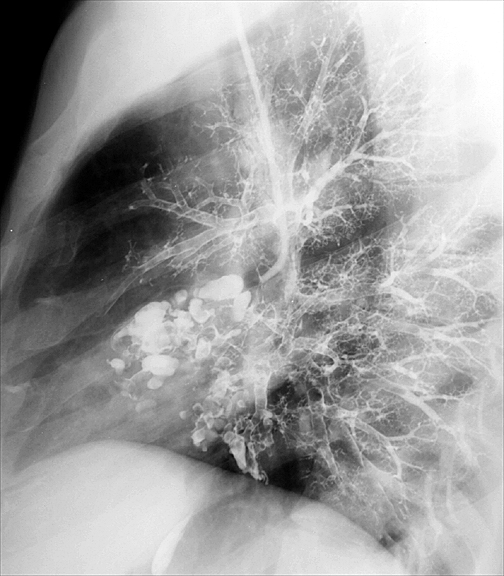

Case 3 Lat bronchogram